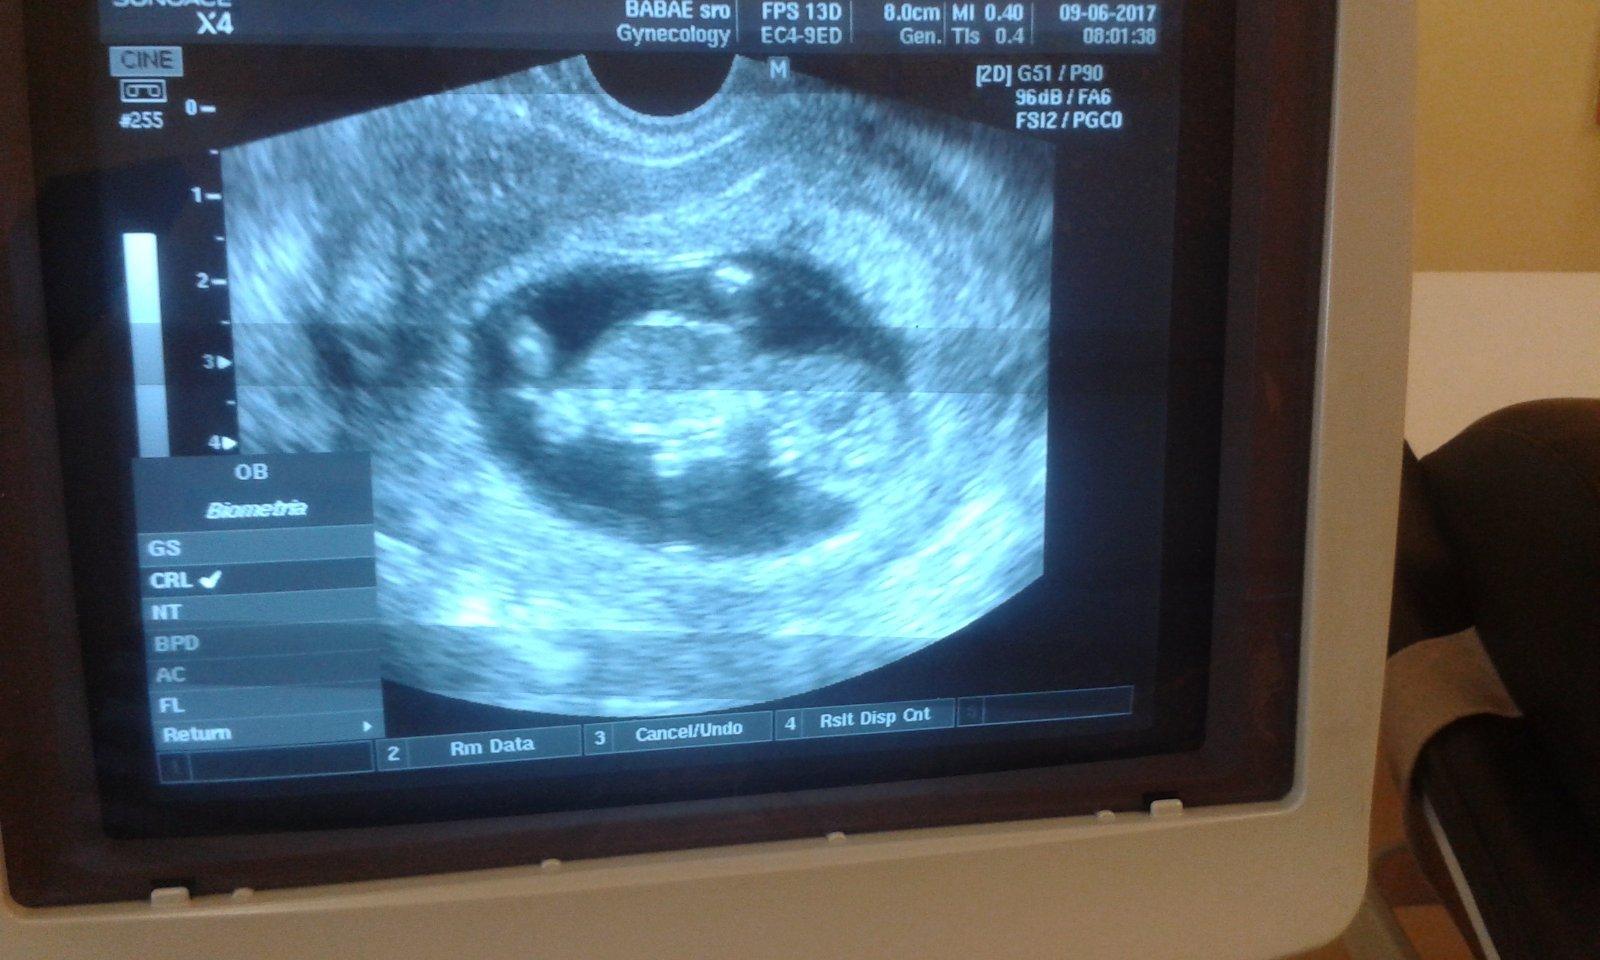

@olylili ahojky.tak vsetko ok.babuliatko pekne rastie som 11+2 ...vzali mi krv a konecne mam tehu knizku😍

@kotatko12345 tak super ked je vsetko ok uz aby ste rastli dalsia paradnu kedy mas meral teraz vam aj NT

ano vsetko merali... 😉

@kotatko12345 koľko máš nt?